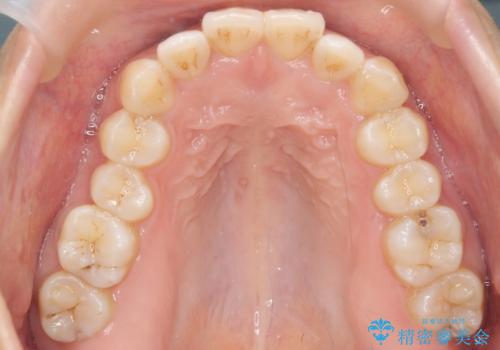

下の前歯のがたつき インビザラインで

- 前歯のがたつきを主訴に来院。

インビザラインで上下の前歯をわずかに削って並べました。

下の歯の叢生を並べると多少ブラックトライアングルがでることがあります。